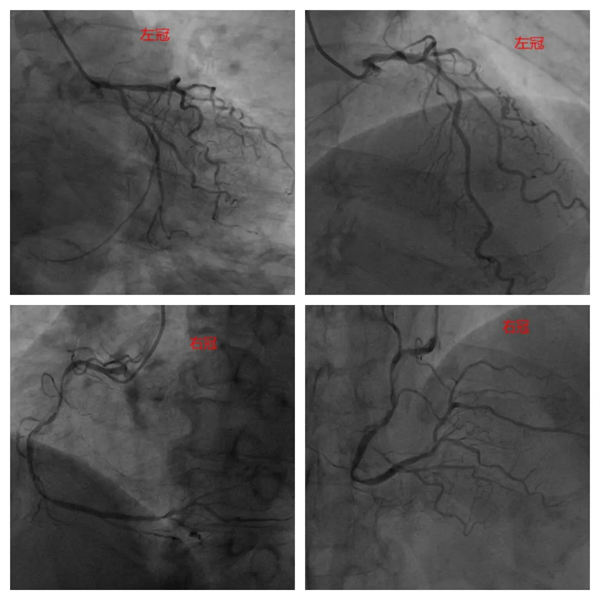

患者術前造影顯示:RCA全程彌漫性鈣化病變,近-中段狹窄70-90%,遠段狹窄70%。LM鈣化狹窄50%;LAD近段鈣化狹窄60-70%,D1近段狹窄60%;LCX近段鈣化狹窄50%,遠段狹窄70%。

術前造影影像